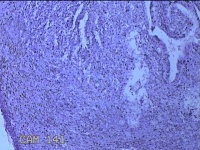

宫腔内容物

性别

女

年龄

36岁

临床诊断

1.异常子宫出血:子宫内膜增厚 2.乙肝 3.慢性宫颈炎 4.子宫肌瘤

一般病史

阴道流血16天,头晕、乏力3天。

标本名称

大体所见

灰白暗红色不规则碎组织3.5x2.8x0.8cm一堆。